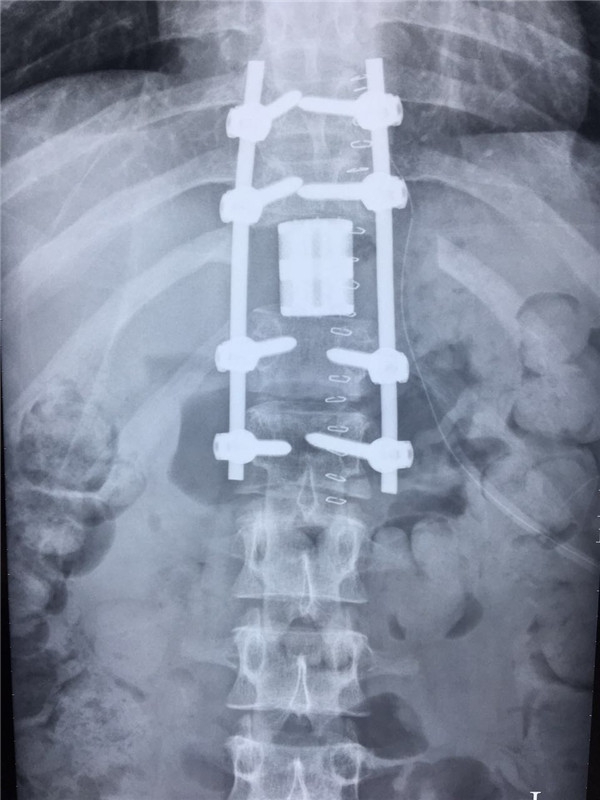

术后 正位